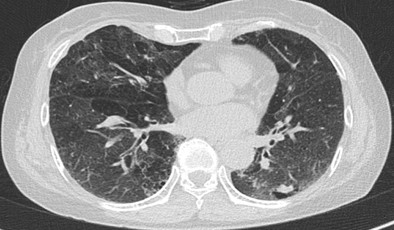

還有一些少見病種:金屬加工液相關(guān)性過敏性肺炎、熱浴盆肺、游泳池肺泡炎、霧噴泉肺泡炎、羽絨被肺等。

五、纖維化性過敏性肺炎的危害和治療

過敏性肺炎診療相關(guān)經(jīng)驗(yàn)嚴(yán)重缺乏,不同地區(qū)臨床實(shí)踐存在很大差異,纖維化/慢性過敏性肺炎很可能被誤診為特發(fā)性肺纖維化或其他特發(fā)性間質(zhì)性肺炎。自1700年發(fā)現(xiàn)間質(zhì)性肺炎以來,許多致敏原被證實(shí)與其有關(guān),但仍有約60%的患者即使有詳細(xì)的病史也無法確定潛在的致敏原。纖維化性間質(zhì)性肺炎如果不治療對(duì)身體危害極大,可繼發(fā)呼吸衰竭、肺動(dòng)脈高壓、肺大泡、自發(fā)性氣胸等。早期診斷和避免接觸過敏原是治療的關(guān)鍵。對(duì)激素和/或免疫調(diào)節(jié)劑治療無反應(yīng)的進(jìn)展性患者,只能考慮肺移植。